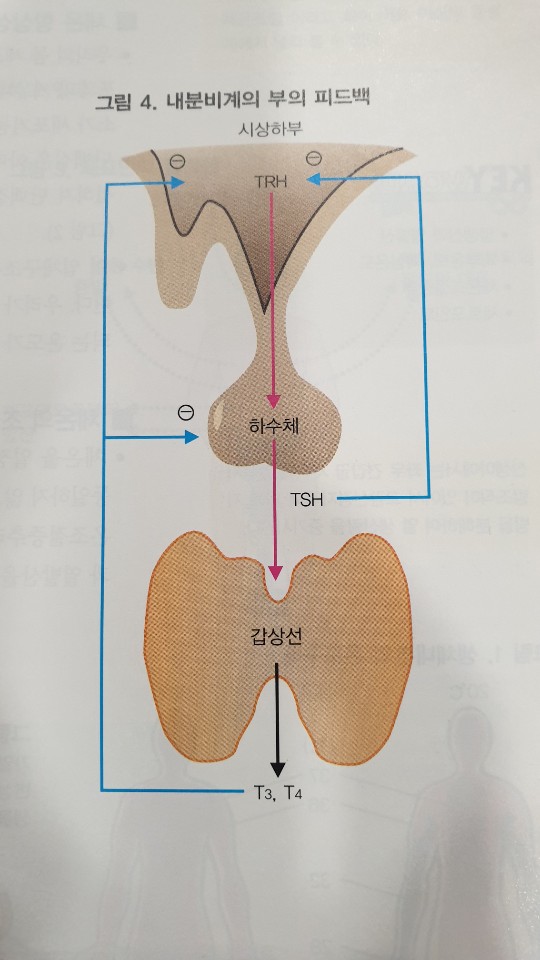

이렇게 보면 뭔가 쉽게 정리가 돼요.TRH는 갑상선 자극 호르몬 분비 호르몬입니다.시상하부에서 뇌하수체를 자극하여 TSH(갑상선자극호르몬) 분비를 촉진시킵니다.이렇게 자극을 받아 뇌하수체에서 분비된 TSH가 갑상선에 작용하여 T3, T4를 분비해 버립니다.

이해되세요?시상하부로부터의 TRH 분비 → TRH가 뇌하수체 전엽 자극 → 뇌하수체 전엽으로부터의 TSH 분비 → TSH가 갑상선 자극 → 갑상선에서 T3, T4 분비. 이렇게 정리할 수 있지요.물론 T3, T4 이외에 rT3, free T4 등의 갑상선 호르몬이 있습니다만, 우선은 이렇게 정리합니다.

이런 갑상선 호르몬은 음성 되감기라는 메커니즘에 의해 그 양이 조절됩니다.예를들면,빵집에지금빵재고가많이남았다면빵을조금만만들지마세요.라고지시해서인기있는빵이두세개밖에남지않았다면조금더빨리만들어달라고지시할것입니다.

마찬가지로 갑상선 호르몬(T3, T4)이 부족한 경우 뇌하수체에서 TRH가 분비되고 시상하부에서 TSH가 분비되며 이는 갑상선을 자극하여 호르몬 분비를 촉진시킵니다. 반대로 몸에 갑상선 호르몬이 과다한 경우 TRH 분비 저하, TSH 분비 저하에 의해 갑상선 호르몬의 생성을 억제합니다.너무 쉽죠?